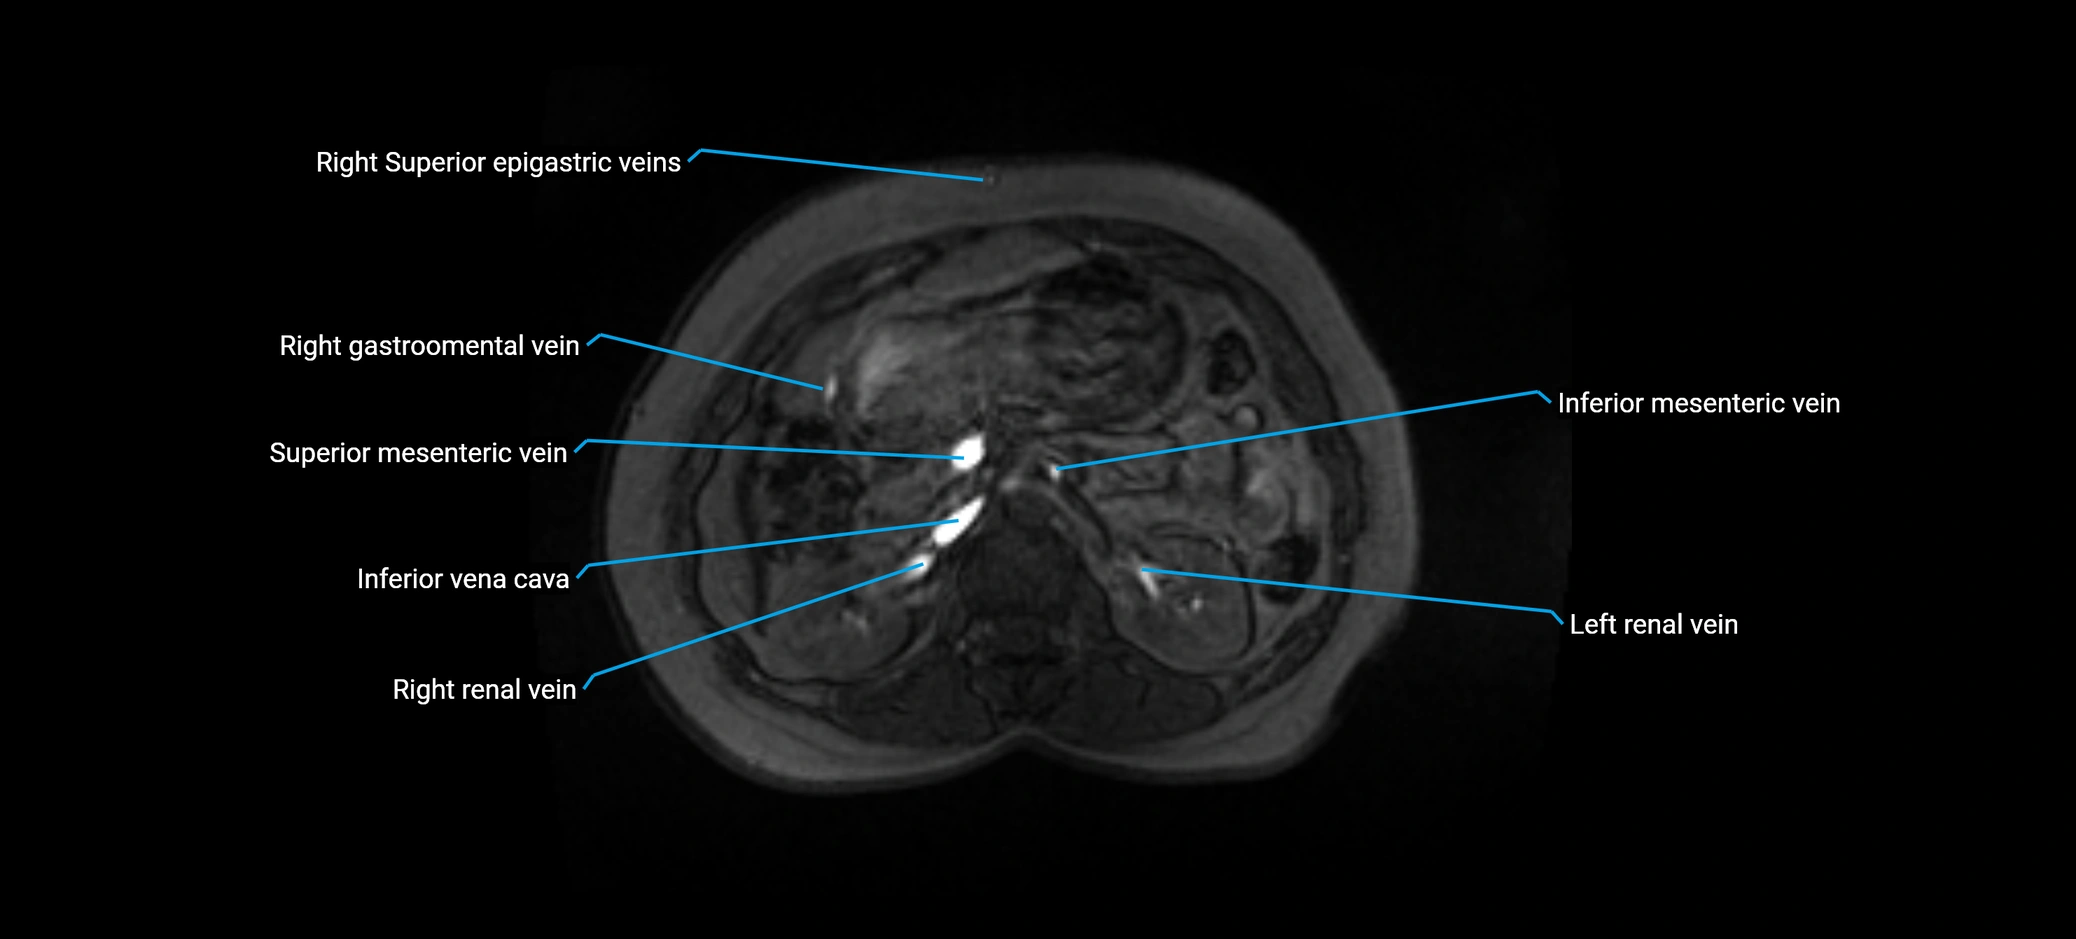

MRI image

image